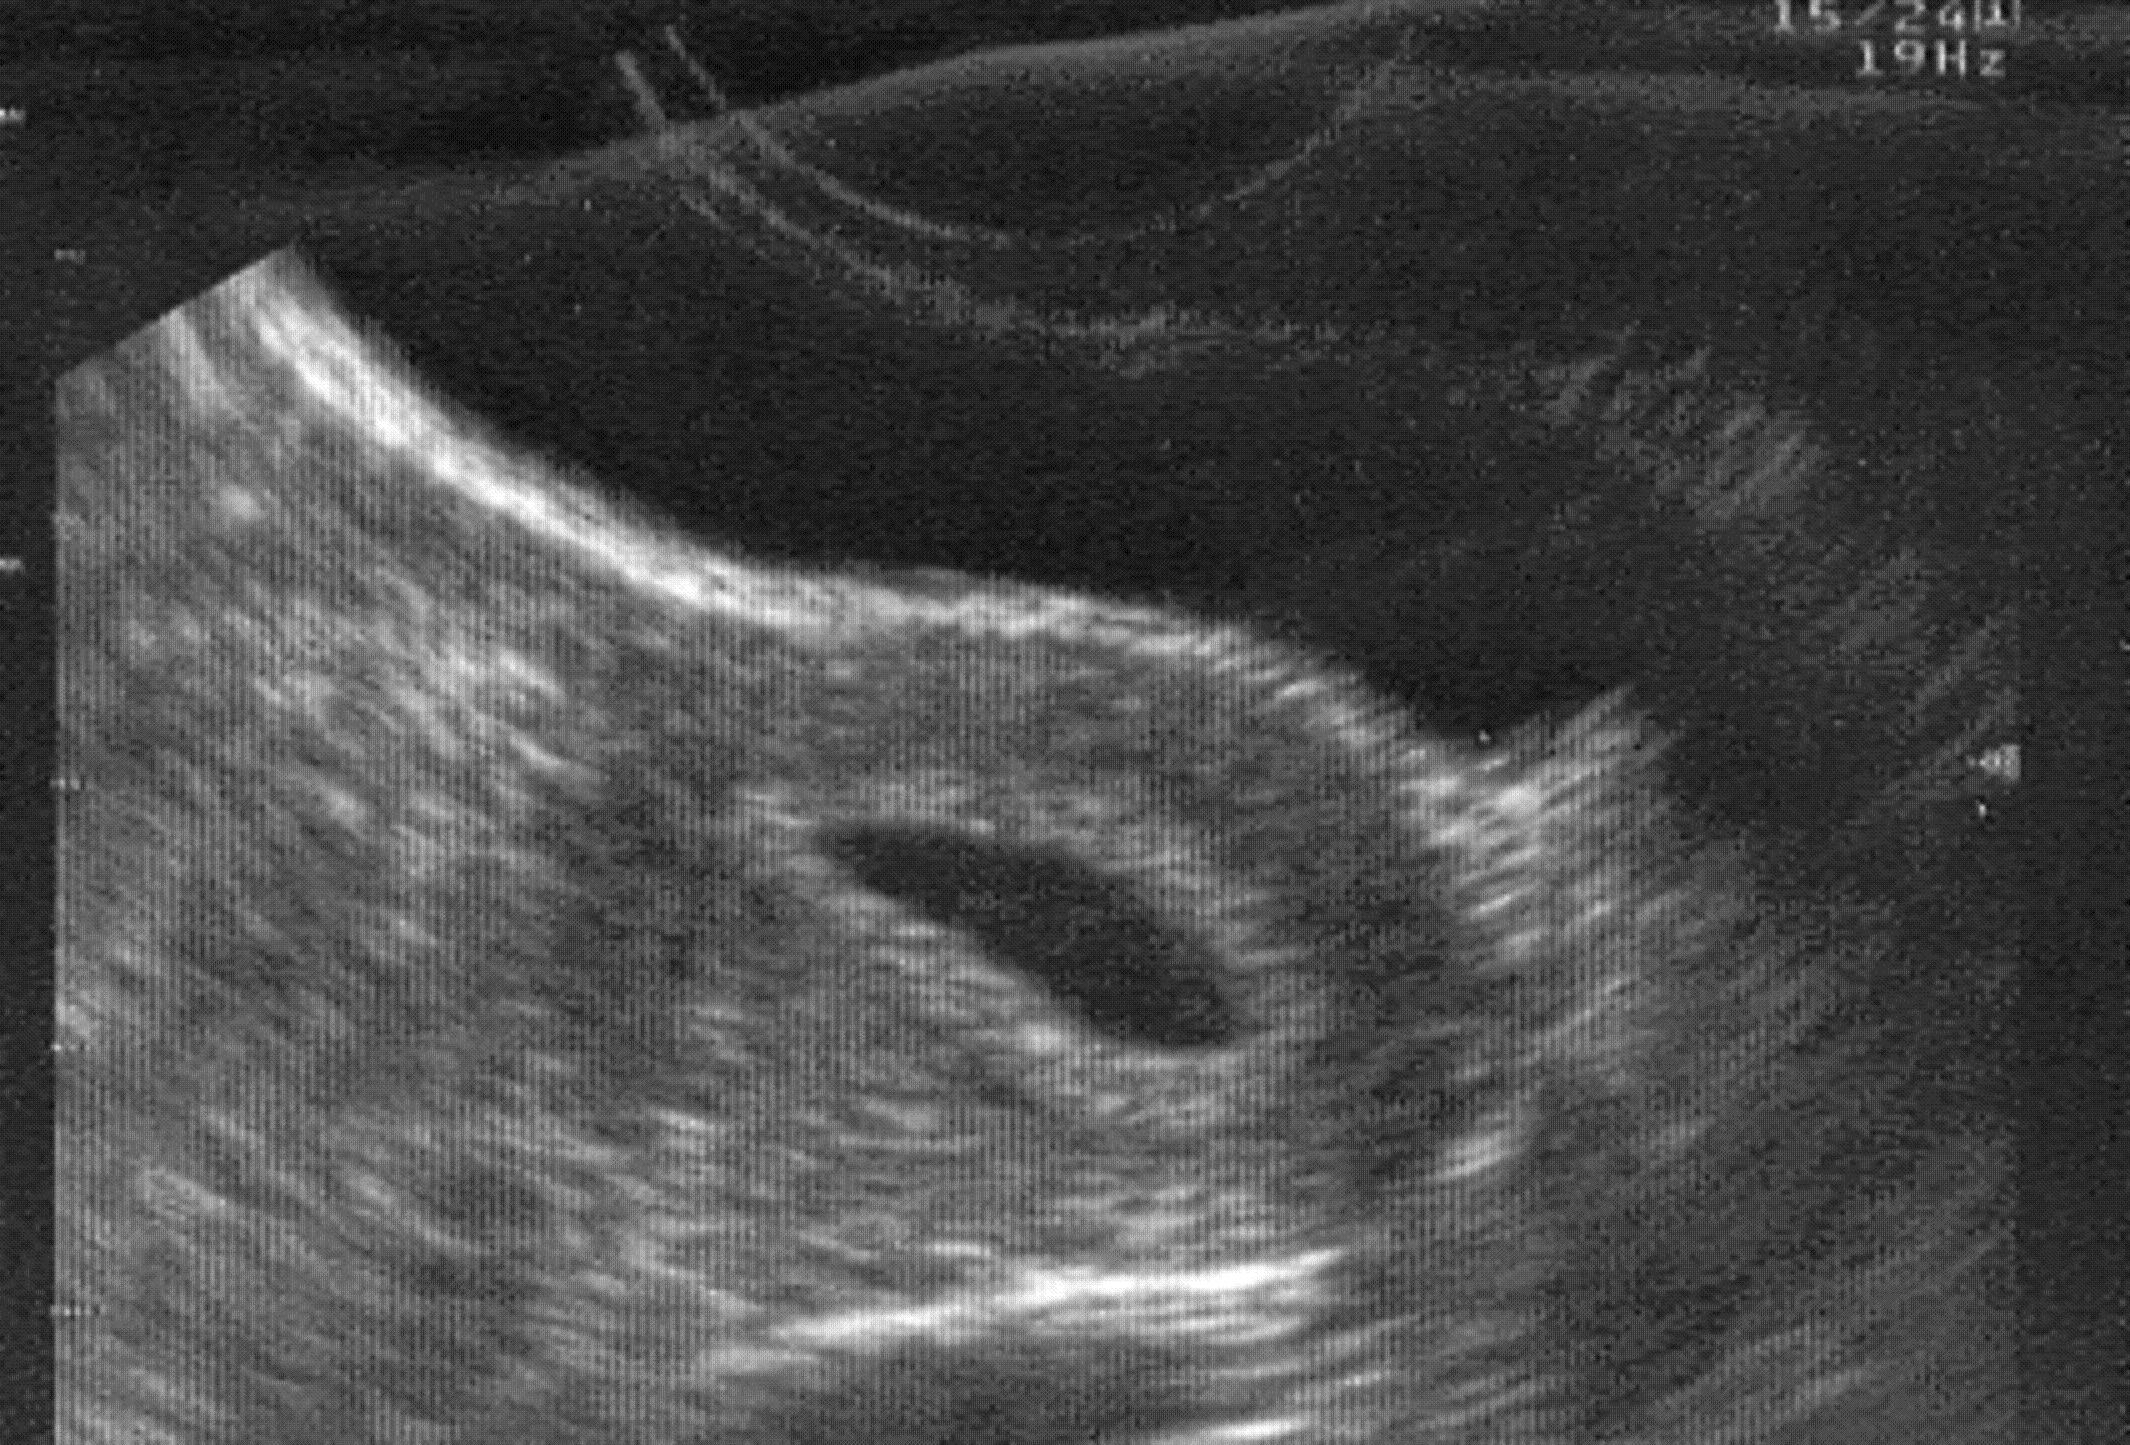

L'échotomographieDéfinitionEnregistrement et analyse des échos de différents milieux et structures organiques, causés par l'application des ultrasons. Cette technique est notamment employée pour surveiller la grossesse. a, en gynécologie, un intérêt plus limité qu'en obstétrique, cependant dans de nombreuses situations elle est indiquée. L'échographie par voie vaginale a constitué un progrès incontestable, il reste cependant licite dans certaines situations de compléter l'examen par voie vaginale par l'échographie par voie sus-pubienne.

Pathologie ovarienne

L'échographie permet surtout de bien visualiser les ovaires qui, par leur situation profonde sont difficiles à explorer cliniquement. Toute la pathologie ovarienne sera donc une indication potentielle à l'échographie. On peut utiliser l'échographie dans le bilan d'une tumeur pelvienne afin de reconnaître la nature de la masse : liquidienne, on évoquera un kyste ovarienDéfinitionPetite poche remplie de liquide développée aux dépens d'un ovaire. Il s'agit d'une affection extrêmement fréquente, découverte la plupart du temps de manière fortuite au cours d'un examen d'imagerie (échographie par exemple). Ces kystes sont bénins dans la grande majorité des cas, et ont des causes variées. (voir kyste ovarien) ; solide, on évoquera une tumeur ovarienne (parfois maligne) ou un fibromyome utérin.

L'échographie reste indispensable lors d'une stimulation ovarienne et, en cas de FIVETE, pour la surveillance de la croissance folliculaire et la ponction des follicules mûrs : on utilise alors une sonde vaginale.